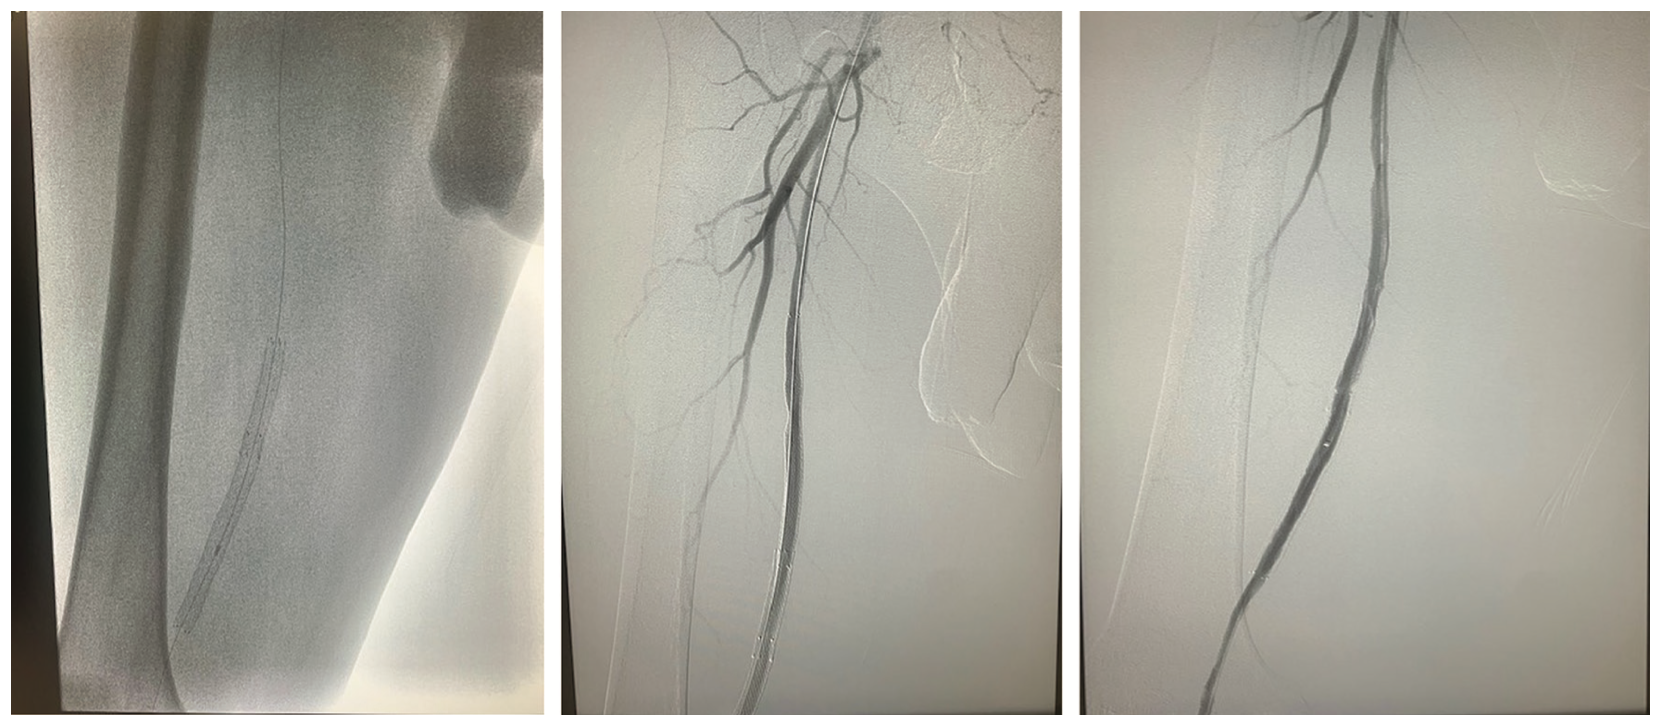

The .035-inch microcatheter was advanced from the contralateral sheath to the bifurcation and the retrograde wire was advanced into the microcatheter. The .035-inch catheter was then advanced over the retrograde wire beyond the distal cap. The retrograde wire was removed, and an antegrade .014-inch ViperWire (CSI) was advanced and externalized. The Touhy Borst adaptor was placed on the externalized wire to prevent withdrawal and allowed work to be performed over the wire in a typical antegrade fashion. A 1.5 Auryon laser (AngioDynamics) (Figures 3-4) was used to perform atherectomy for a total time of approximately 3 minutes. Following atherectomy, a 6.0 mm x 240 mm noncompliant balloon was utilized to dilate the vessel. Inflation at 4 atmospheres resulted in patient pain, but a slightly higher pressure was done at the stent overlap. Angiography revealed brisk flow through the vessel, but there was clearly dissection proximal to the previous stents. Two prolonged inflations of 5 minutes were performed without significant improvement in the dissection. A stent was subsequently placed to address the dissection, followed by postdilation with the balloon at higher pressure, which resulted in good flow through the vessel without any residual angiographic dissection (Figure 3).

Retrograde dissection and re-entry, like antegrade dissection and re-entry, typically involves subintimal passage of a wire directed toward the proximal cap. Re-entry can be performed using the techniques mentioned above or the wire can be left in place as a marker wire to help direct antegrade wire escalation, particularly when there is an ambiguous proximal cap. Antegrade wire escalation or retrograde wire escalation can also be used to modify plaque and facilitate true lumen entry, as in our case. As our equipment was advanced to overlap the “knuckles” and set up for reverse CART, the antegrade knuckle collapsed, which suggests it had entered the same space as the retrograde equipment. The wire was advanced from the retrograde space into the contralateral sheath. A “tip in” technique was then utilized to externalize the wire in an antegrade fashion to complete the case.6 The “tip in” is similar to the “rendezvous” technique; however, in the latter, the retrograde microcatheter is intubated with the antegrade wire. The tip in technique is typically utilized when a retrograde wire crosses into the true lumen, but a microcatheter is unable to follow. The retrograde wire is advanced to the outer curve of the sheath (usually the iliac bifurcation) and the antegrade microcatheter is intubated by the retrograde wire. Physics dictates that both pieces of gear should meet at the outer curve. In the peripheral space, this can be facilitated, since one can use either an .018-inch or .035-inch microcatheter. Once the wire is intubated, the sheath can be advanced over the retrograde wire. In this case, once this was achieved, a ViperWire was advanced distally and externalized from the pedal access. Laser atherectomy was then performed with the Auryon laser with subsequent percutaneous transluminal angioplasty and stenting of the SFA with establishment of straight-line flow to the foot. The ViperWire serves as a good externalization wire, as it is a 325 cm wire. The R350 (Teleflex) is also a good externalization wire, as it is 350 cm in length.